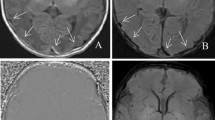

A comparative analysis of APT MRI and SWI in identifying ICH

Figures 1, 2 and 3 showed the imaging manifestations of ICH at hyperacute, acute and subacute stages, respectively. Table 1 quantitatively compared the APT-weighted (APTw), magnetization transfer ratio (MTR)(3.5 ppm) and SWI signal intensities between ICH at hyperacute, acute and subacute stages and the corresponding contralateral normal brain tissue. The APTw signal intensity was significantly higher in the ICH at hyperacute, acute and subacute stages than that in the contralateral normal brain tissue (all p < 0.001). The MTR(3.5 ppm) signal intensity was significantly lower in the ICH at hyperacute, acute and subacute stages than that in the contralateral normal brain tissue (p = 0.03, 0.01 and <0.001, respectively). The SWI signal intensity was significantly lower in the ICH at hyperacute and acute stages than that in the contralateral normal brain tissue (p = 0.03 and 0.02, respectively), but we observed no significant difference between the subacute ICH and the contralateral normal brain tissue (p = 0.11). After Bonferroni corrections for multiple comparisons, the APTw signal intensity was significantly higher in the hyperacute ICH than that in the subacute ICH (p = 0.014).

The hematoma shows mixed-signal on (a) T1w image and (b) T2w image. (c) Susceptibility weighted imaging (SWI) image shows an isointense center with a hypointense periphery. (d) Amide proton transfer (APT) image shows hyperintense signal. (e) MTR(3.5 ppm) image shows hypointense signal. (f) Z spectra map. (g) Z spectra asymmetry curve map.

The hematoma shows isointense signal on (a) T1w image and hyperintense signal on (b) T2w image. (c) SWI image shows a hyperintense center with a hypointense periphery. (d) APT image shows hyperintense signal. (e) MTR(3.5 ppm) image shows hypointense signal. (f) Z spectra map. (g) Z spectra asymmetry curve map.